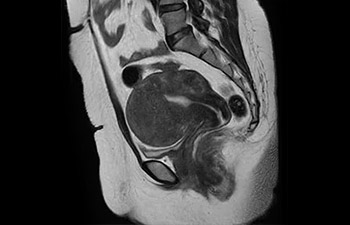

• Baanbrekende versnellingstechniek waarmee niet alleen sequenties versneld worden, maar uw gehele MRI-onderzoek. • Unieke implementatie waarmee 2D- en 3D-scans tot wel 50% sneller gemaakt kunnen worden met een nagenoeg gelijkwaardige beeldkwaliteit.1

• Kan gebruikt worden in alle anatomische contrasten en alle anatomieën.

1 In vergelijking met Philips-scans zonder Compressed SENSE. Resultaten van casestudy's bieden geen voorspellingen voor resultaten in andere gevallen. Resultaten in andere gevallen kunnen variëren.